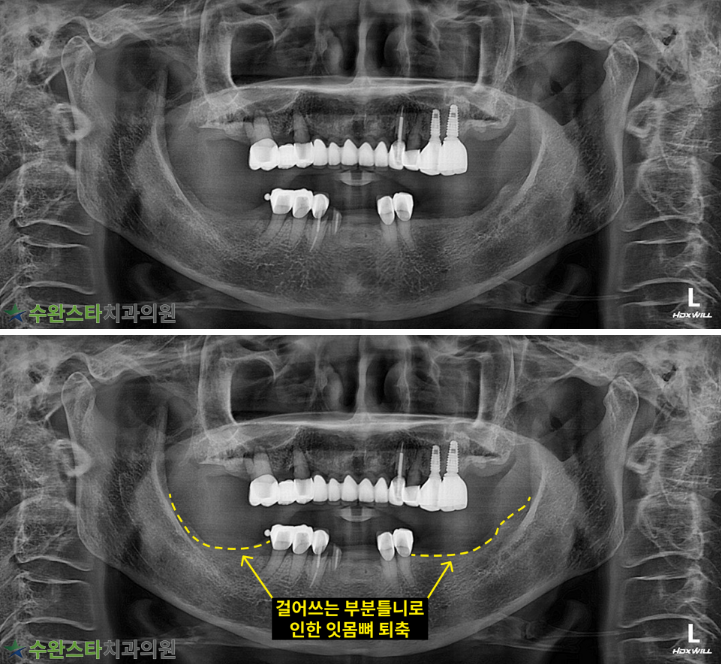

내원 시 파노라마

처음 내원 시 파노라마, 80대 여성 (2025.8 촬영)

내원 시 파노라마 사진입니다.

장기간 틀니 사용으로

아래쪽 잇몸뼈가 심하게

퇴축되었습니다.

잇몸뼈가 많이 녹은 경우

자연치아를 살릴 수 없어

발치 후 뼈 이식과 임플란트가

필요합니다.